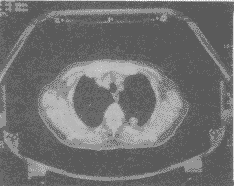

1.5 扫描图像后处理:按照X-刀治疗的要求摄片图像大小保证体箱架的5个标志点清晰可见(附图)。记录下滑板、Z轴、弓形尺、腹带值和其它有关数值,并在体表作出标记;在得到病人图像后,再在每一层面上精确地勾画出靶区的轮廓和周围重要组织如脊髓等。然后将CT图像通过专用的微机和扫描仪送入工作站的体部X-刀治疗计划系统中,为X-刀治疗提供依据。

附图 X-刀治疗的CT定位图像。X-刀体箱架的5个标志点清晰可见